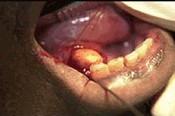

男性,36岁。进食时左侧颌下区肿胀疼痛,进食后数小时方可逐渐消退。下颌下腺导管开口处红肿,轻压腺体导管口溢脓。

检查见图示,以下哪项检查有助于进一步确诊 ( )

男性,36岁。进食时左侧颌下区肿胀疼痛,进食后数小时方可逐渐消退。下颌下腺导管开口处红肿,轻压腺体导管口溢脓。 检查见图示,以下哪项检查有助于进一步确诊 ( )

A曲面断层片

B下颌骨后前位片

C下颌前部颌片

D下颌下腺造影

E下颌横断颌片